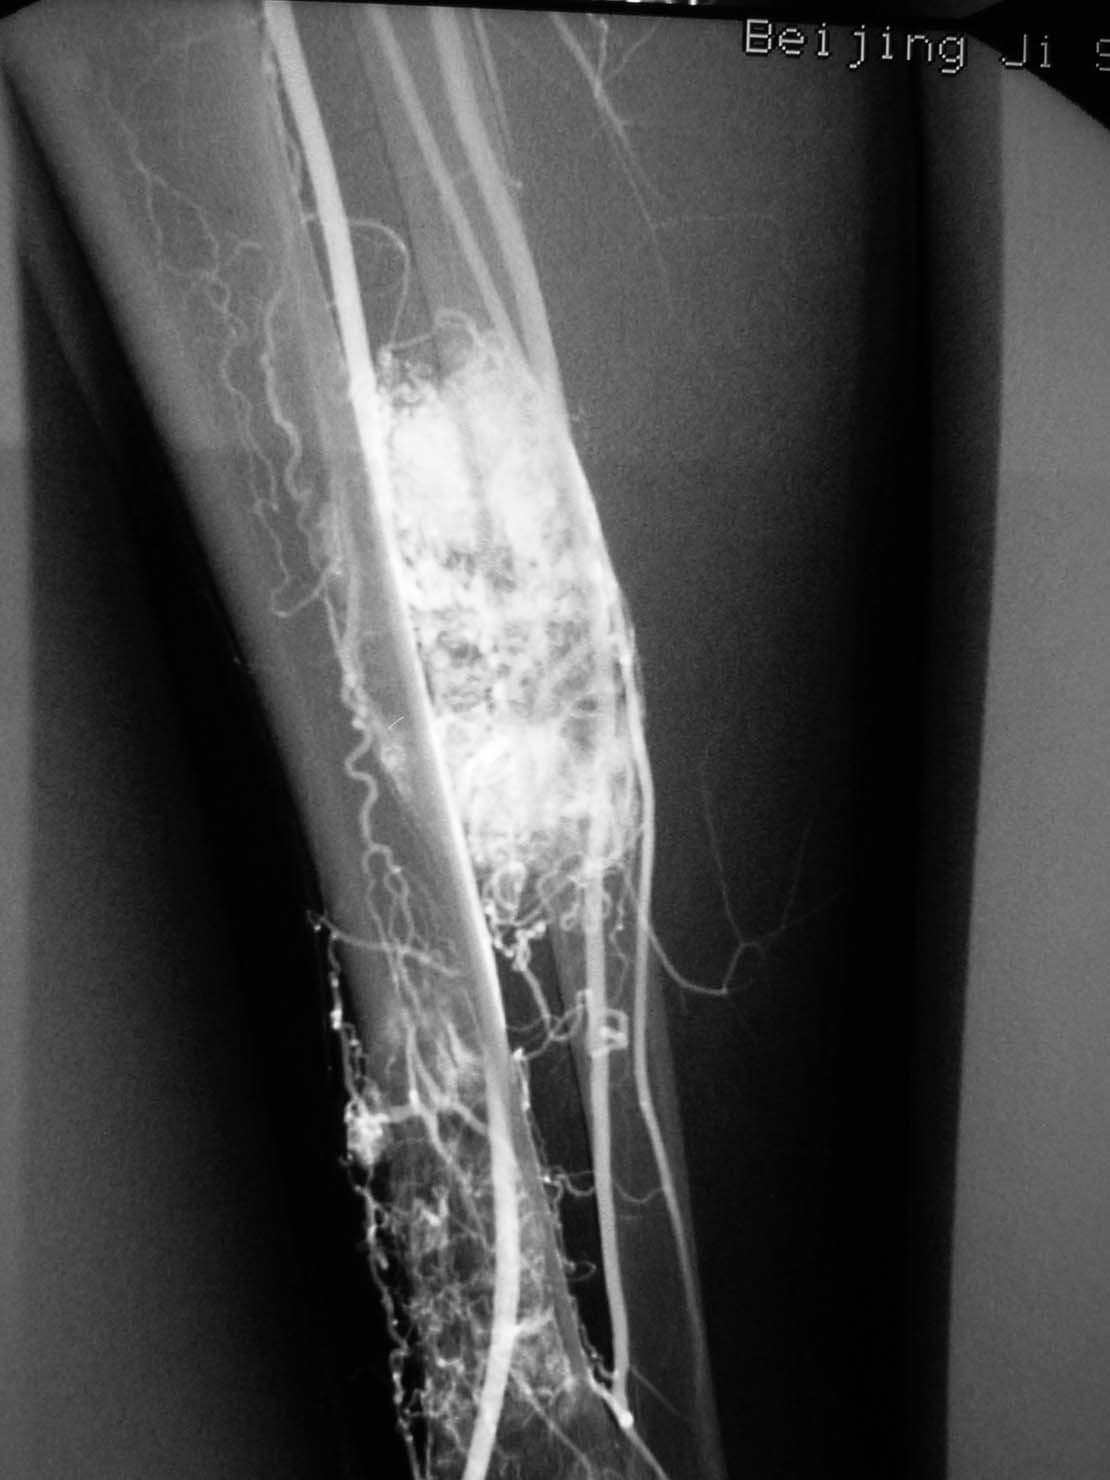

腺泡样软组织肉瘤

[emb14]

极为罕见,其组织来源不明。

起源于肢体软组织者称腺泡状软组织肉瘤,原发于骨内者,称骨腺泡状肉瘤。

本病大多发生于股部、臀部及小腿深侧肌群,上肢和其他部位少见。

x线平片:圆形或卵圆形软组织肿块影,基底部与病骨相连。

肿瘤内可见斑点状或细小结节状钙化。

骨质破坏大多表现为溶骨性地图状或虫噬性破坏,并常伴有层状骨膜反应。

mr检查:t1和t2加权像均显示肿瘤组织呈分叶状高信号强度,并见肿瘤内有低信号间隔。